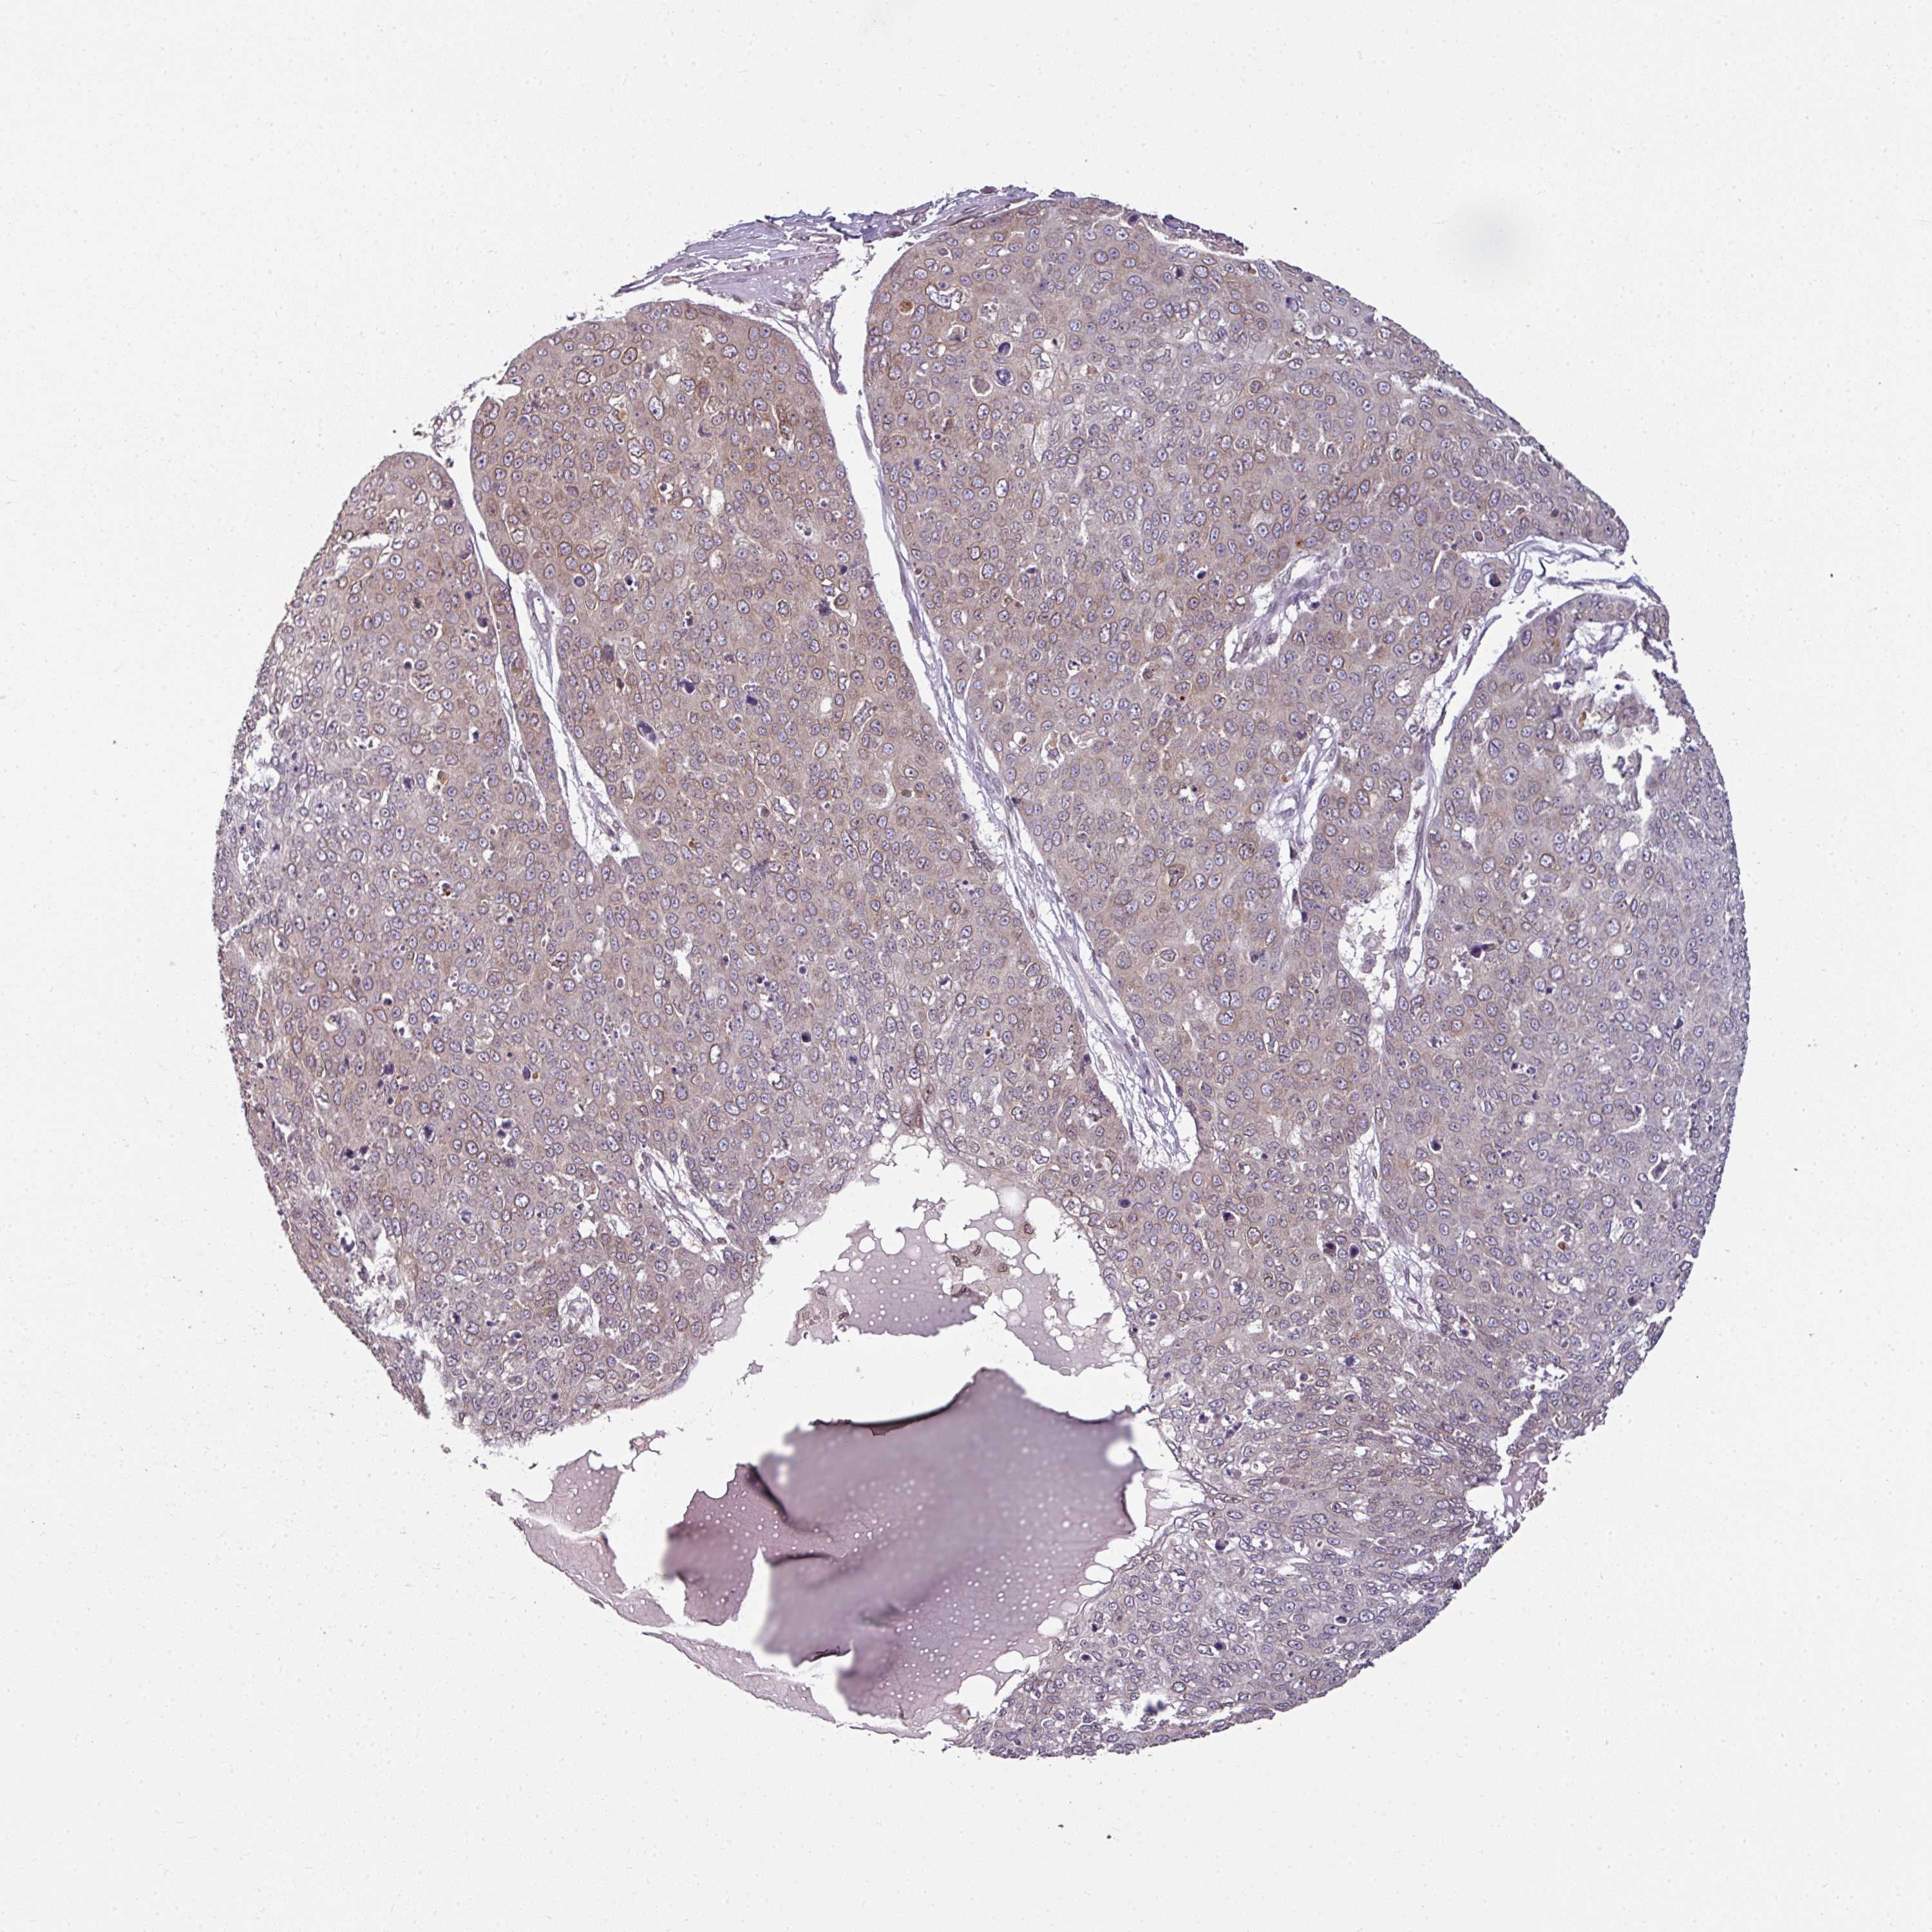

Basal cell and squamous cell cancer

SKIN CANCER - Protein expressioni

A mouse-over function shows sample information and annotation data. Click on an image to view it in a full screen mode. Samples can be filtered based on level of antibody staining by selecting one or several of the following categories: high, medium, low and not detected. The assay and annotation is described here.

Each image is clickable and will lead to virtual microscopy that enables deeper exploration of all samples and also displays staining intensity scores, fraction scores and subcellular localization as well as patient and tissue information for each sample.

Antibody HPA050110

Antibody CAB004293

Staining

High

Medium

Low

Not detected

Intensity

Strong

Moderate

Weak

Negative

Quantity

>75%

75%-25%

<25%

None

Location

Nuclear

Cytoplasmic/membranous

Cytoplasmic/membranous,nuclear

Basal cell carcinoma

Squamous cell carcinoma, NOS

Squamous cell carcinoma, metastatic, NOS